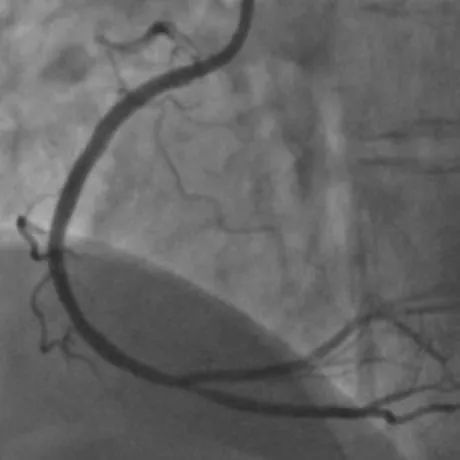

现场医生立刻电话联系心内科,必须尽快恢复患者冠脉灌注!门诊部进行快速核酸检测,但核酸结果出来至少需要几个小时,没有核酸结果,增加了疫情防控风险,但是在生命面前,及时救治更为重要!陈红主任和刘健副主任果断决定立即启动胸痛中心绿色救治通道,升级防护尽快为患者实施介入手术。冠脉造影证实了心电图的结果右冠状动脉近段和中段80%,99%狭窄。医护人员披上铅衣铠甲,穿戴上密不透风的防护服和防护面罩。术者、助手、护士、技师每个人都精神高度集中,分工明确,紧密协作。

16:00,宋俊贤和张静医生迅速完成导丝通过球囊扩张及支架置入,而此时距离患者发生胸痛仅有60分钟,达到了急性心肌梗死治疗指南中FMC-to-W(首次医疗接触到导丝通过)不超过60分钟的国际标准,时间就是生命,时间就是心肌,及早成功开通梗死的血管是救治急性心肌梗死患者关键所在。

在黄金时间窗内,争分夺秒成功开通闭塞的血管,尽可能多的保护了更多心肌。手术非常成功苏阿姨胸闷、胸痛症状随即消失,术后心电图恢复正常。